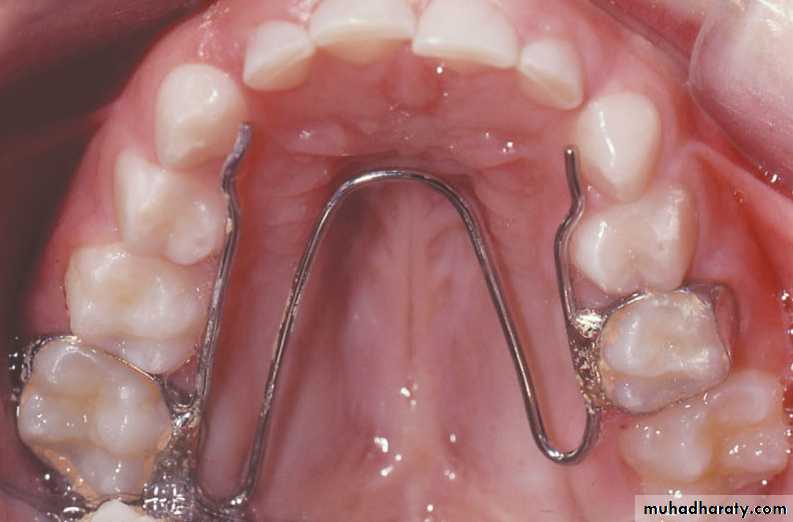

The preferred appliance is adjustable lingual arch that is banded to molars and requires little patient cooperation.

• W arch and quad helix are reliable and easy to use.

Both are constructed from 0.9 mm stainless steel wire and can be adjusted to produce anterior or posterior expansion.

The lingual wire should contact the teeth involved in crossbite.

The appliance is activated by opening it 3-5 mm wider than passive width.

•